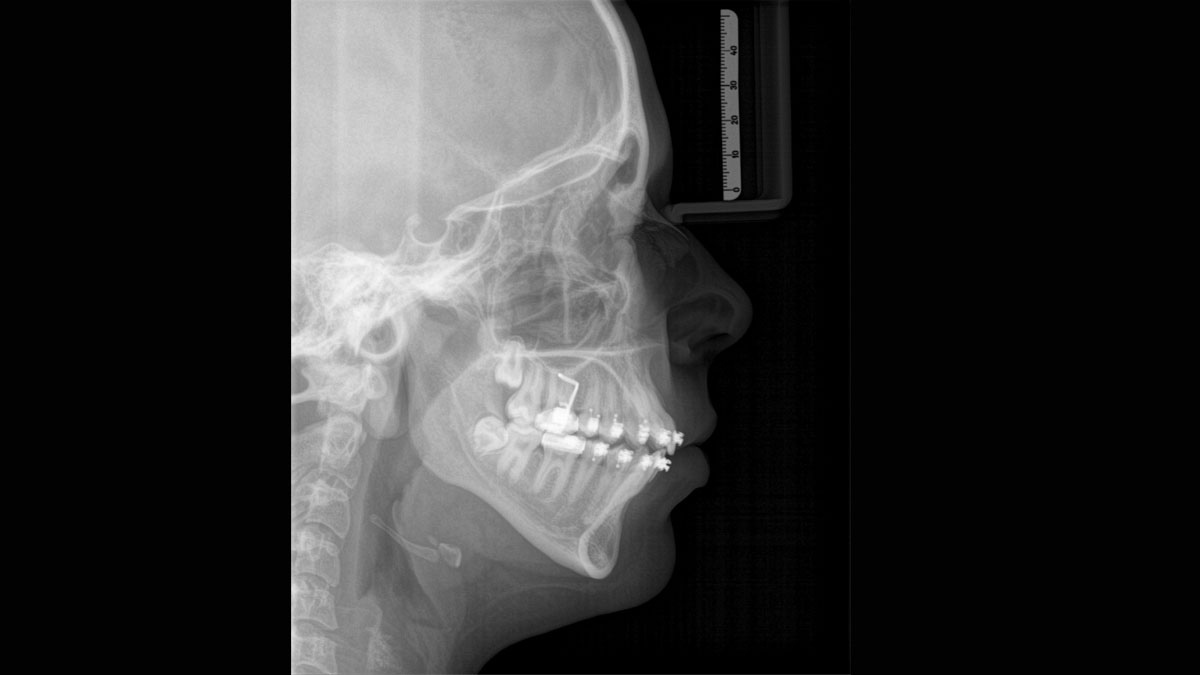

The patented bite block technology, for example, automatically establishes the correct inclination of the patient's head, positioning the patient in the occlusal plane, partnering with the 3 point head fixation and firm handles to ensure stable positioning-limiting unnecessary correction scans.